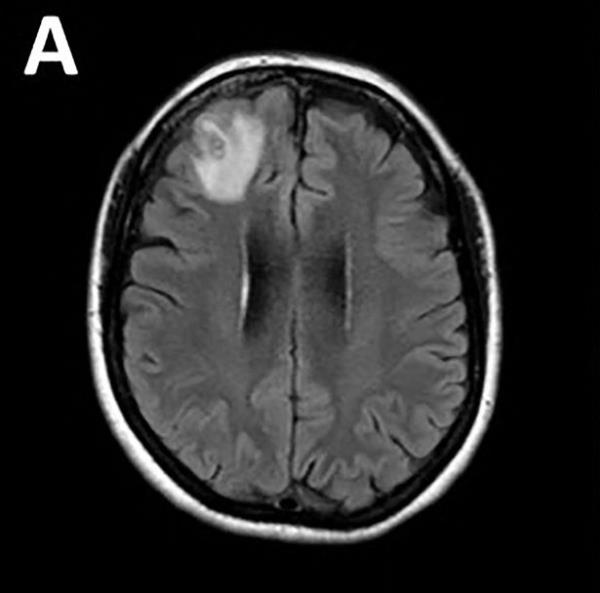

塞纳纳亚克说:“这名患者接受了一种神秘疾病的治疗,我们认为最终是一种免疫疾病,因为我们之前没有找到寄生虫,然后不知从哪里冒出来的,这个大肿块出现在她的大脑前部。”